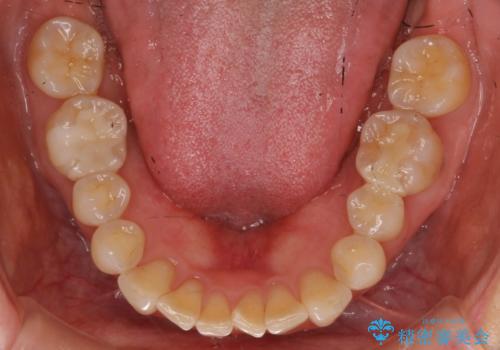

向かい合う銀歯を同時にやり変えることで、コンタクト(歯と歯の間の形)を理想的に仕上げることができ、ものも挟まりにくいように仕上げることができます。